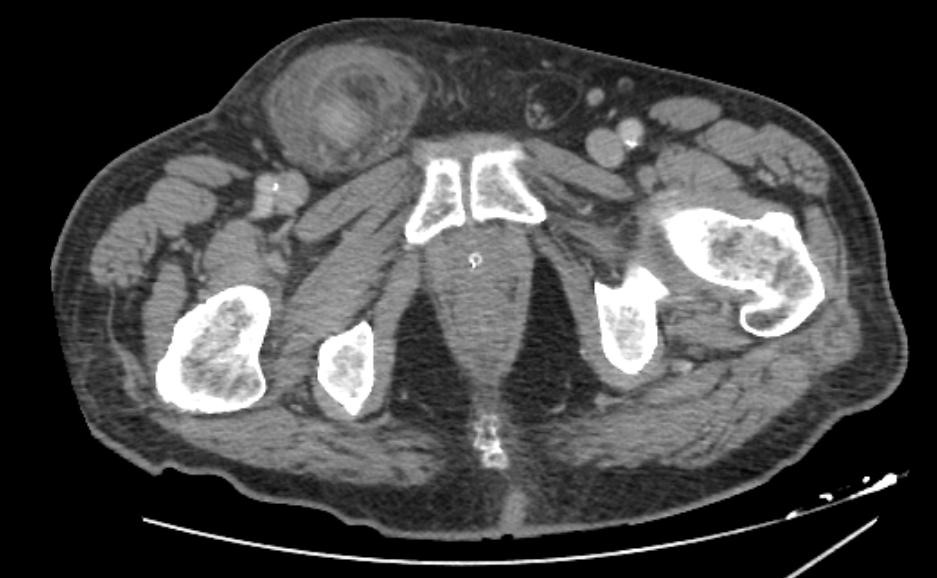

On admission, his vital signs were stable: blood pressure was 125/85 mmHg, pulse rate was 80 bpm and body temperature was 37°C. Physical examination revealed a painful, tender and irreducible right inguinal hernia without signs of peritonitis on abdominal palpation. Laboratory tests showed an elevated C-reactive protein (CRP 112.6 mg/L) as the only abnormal finding, with white blood cell (WBC) count at 2,240/µL and neutrophil percentage at 58.1%. An abdominal CT scan revealed caecal protrusion within the inguinal hernia sac, hyperaemia of the colonic wall, free fluid in the hernia sac and ascites in the peritoneal recesses (figure 1 – 3).

Figure 2 : CT Scan

Figure 2